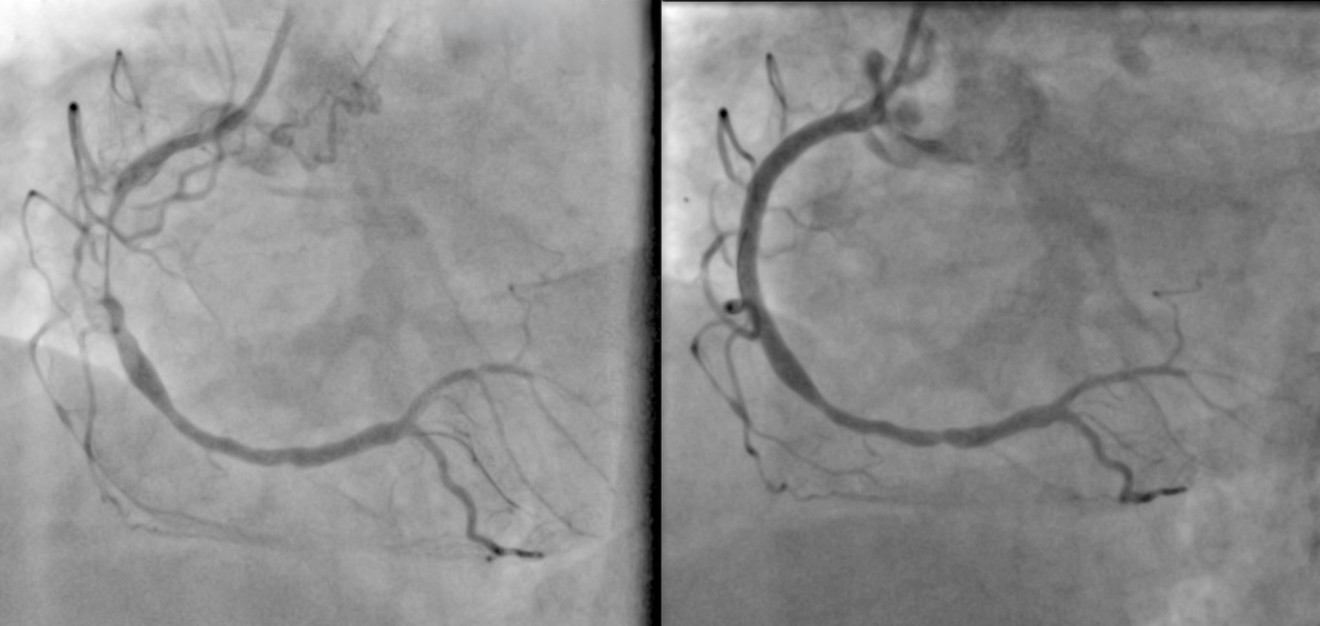

Links Bild: Gefäß vor Rotablation

Rechts Bild: Gefäß nach Rotablation und Stenting